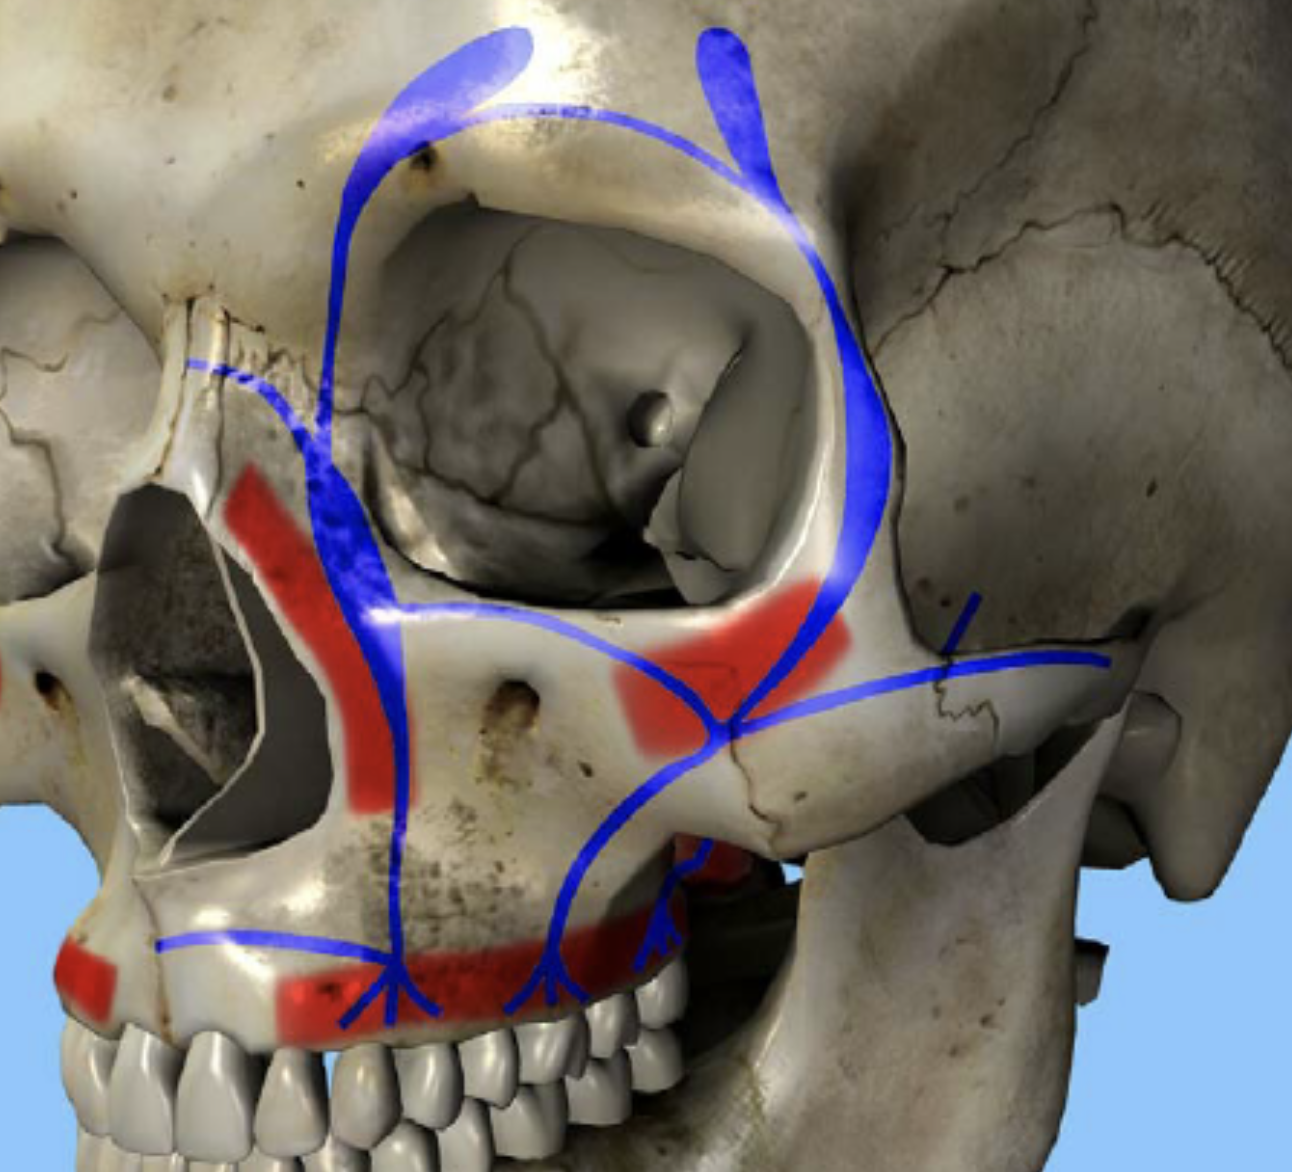

Que représente cette image et quelle fonction ?

Système d'amortissement et de stabilisation absorbant les forces verticales et horizontales

En bleu, piliers de Sicher verticaux : pilier canin, malaire et ptérygoïdien

En rouge, poutres de résistance d’Ombredanne horizontales : inférieure, moyenne et supérieure.